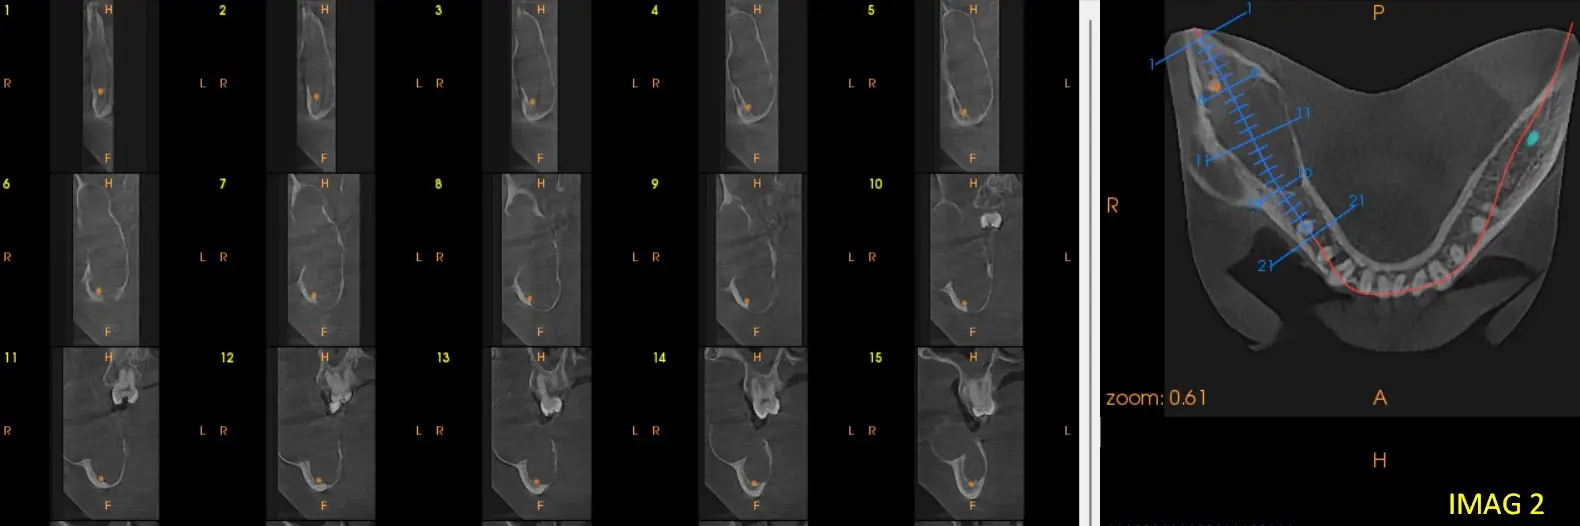

En los cortes sagitales y axiales de CBCT (ver imagen 2 y 3) se evidencia un marcado desplazamiento del conducto dentario inferior hacia el borde basal, acompañado de adelgazamiento y perforación de la cortical ósea, visible en la reconstrucción multiplanar (ver imagen 4). El contenido de la lesión es homogéneo, no se identifican tabiques internos ni calcificaciones que sugieran una lesión fibro-ósea, y la expansión y perforación cortical indican un comportamiento localmente agresivo. Por la combinación de las características: lesión unilocular, sin relación dentaria, desplazamiento del conducto y perforación cortical— el diagnóstico más probable es un ameloblastoma unicístico, considerando como segundo diagnóstico diferencial un queratoquiste odontogénico.